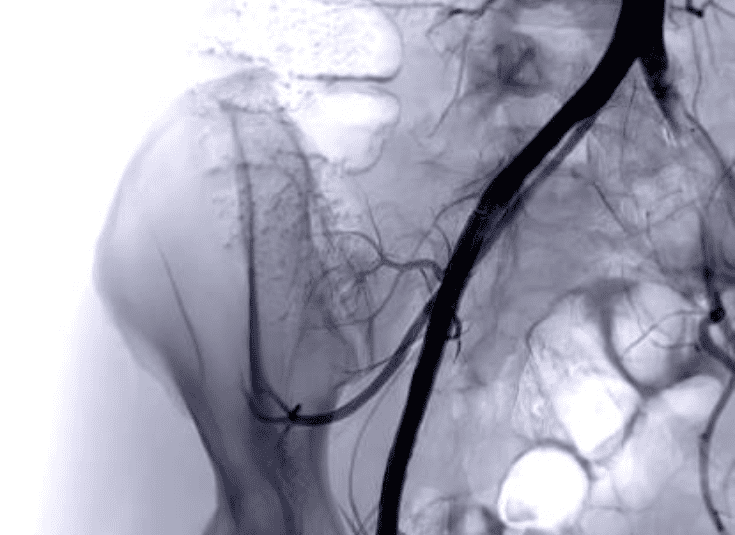

Peripheral Vascular Disease (PVD) refers to the narrowing or blockage of the blood vessels outside the heart and brain, often due to atherosclerosis. PVD can cause significant pain, mobility issues, and, in severe cases, tissue death due to inadequate blood supply. Surgical treatment for PVD aims to restore blood flow to the affected limbs and organs, improving the patient’s overall quality of life and reducing the risk of more severe complications.

Surgical options for PVD include bypass surgery, angioplasty, and stent placement, which help clear or bypass blocked arteries. In some cases, endarterectomy, a procedure to remove plaque from the artery, may be necessary. Advances in surgical techniques, such as endovascular surgery, allow for minimally invasive procedures that reduce recovery time and the risk of complications compared to traditional open surgery.

- Angioplasty to open up narrowed blood vessels.

- Stent placement to keep arteries open after surgery.

- Bypass surgery to reroute blood flow around blockages.

- Endarterectomy to remove plaque buildup from arteries.